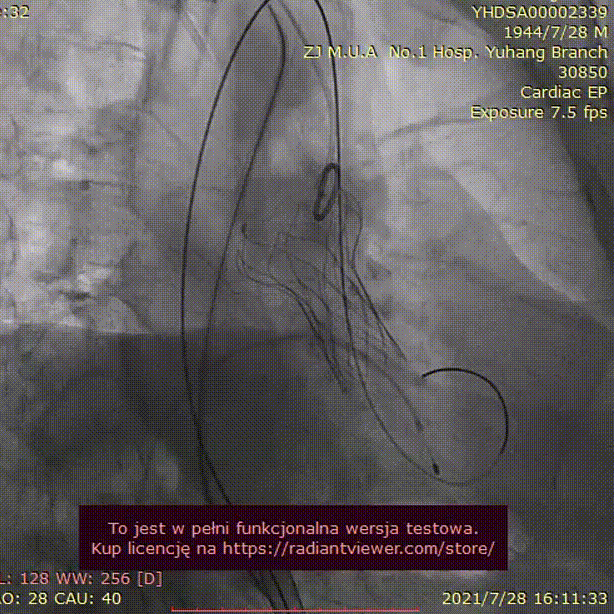

手术过程:

20mm球囊预扩

(无腰征,少量瓣周漏)

TAV24 瓣膜释放前定位

释放过程

植入后造影

术后压差1mmHg

术后结果:测左室-主动脉平均跨瓣压差3mmHg。

术中经食道心超评估: